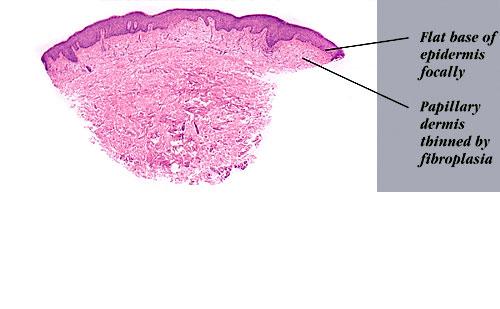

Atlas of skin histopathology

Erythroderma of mycosis fungoides = احمرية الجلد في التفطر الكمئي